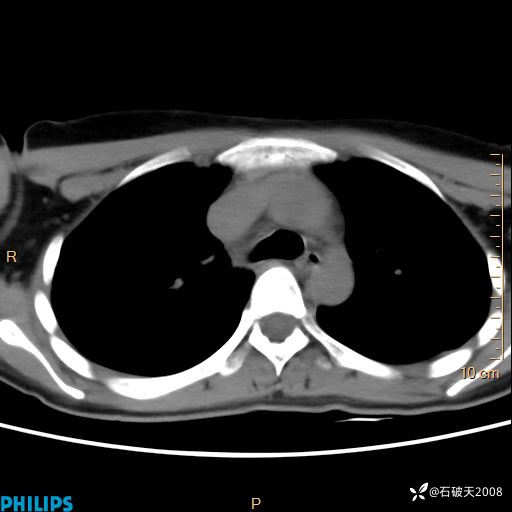

静脉期